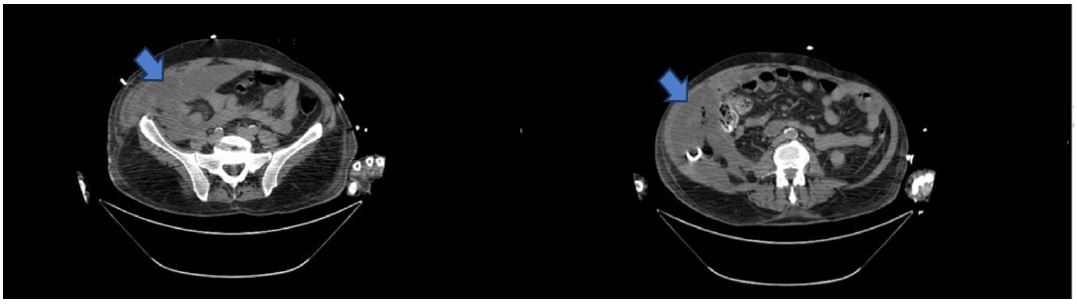

Several days after surgery and once the patient was stabilized, an Endoscopic Retrograde Ccholangiopancreatography (ERCP) was performed. This revealed a high-output bile leak in the distal portion of the main bile duct. The procedure included a sphincterotomy and the placement of a metal bile duct stent (Figure 2).

Figure 2: Image of the ECRP done for treatment of the bile duct leak.